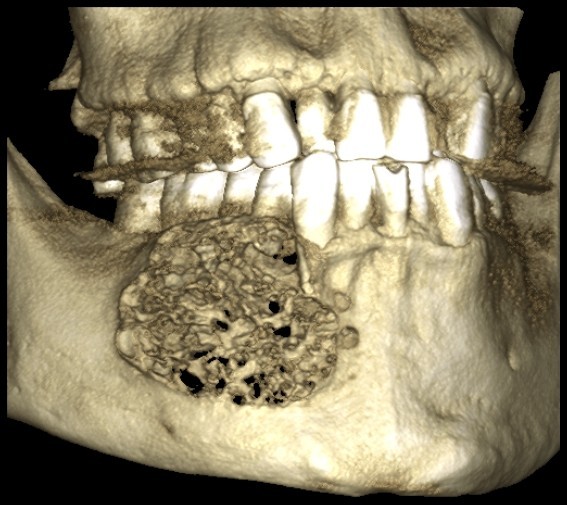

颅颌面CBCT

诊断范围涉及牙体牙髓病、牙周病、阻生牙/多生牙定位、种植牙术前CT评估分析、颞下颌关节CT诊断分析、,颌骨及涎腺疾病、颌面发育畸形、正畸治疗辅助诊断等大部分颌面部疾病,为临床医疗提供强有力的支持。